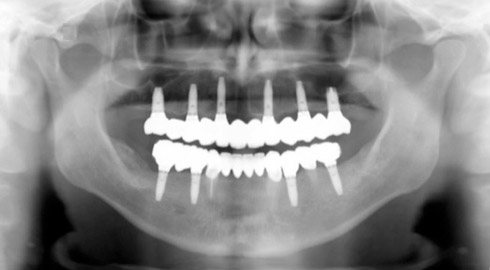

Exemple d’une réhabilitation complète implantaire